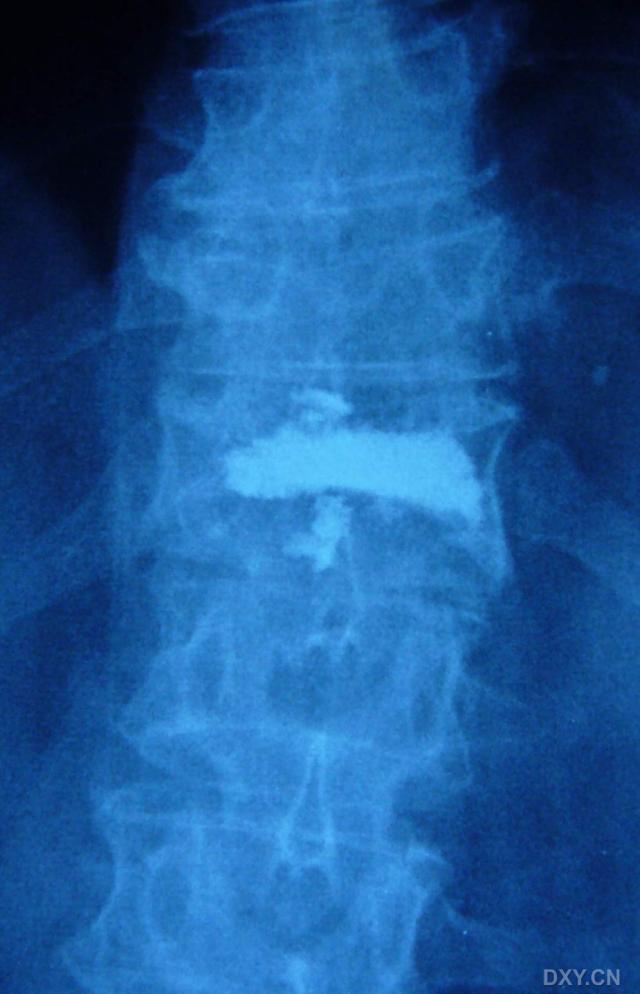

术后X-ray:1为后部先填充,2为前中部后填充,中间还不连续?!

看这个骨水泥的渗漏好像是从前面渗出去的,可能和损伤本身有关系,骨质疏松加上前方可能出现的骨折线。